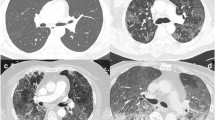

Segmental acute pulmonary embolism in COVID-19 patients: one was a 61-year-old man presenting to the emergency department for fever and myalgia during 9 days with new onset of dyspnea without desaturation. The RT-PCR for SARS-CoV-2 was positive. Unenhanced chest CT scan (a) revealed typical COVID-19 pneumonia with mild lung involvement (TSS of 7). CTPA in axial (b) and coronal reformation (c) showed a segmental acute pulmonary embolism of the right lower lobe (arrows). After 2 days of hospitalization, the patient was discharged at home with a good outcome

Given the risks associated with the injection of iodinated contrast medium (renal failure and allergy) and the additional radiation dose due to CTPA, it does not seem reasonable to perform CTPA systematically with COVID-19 patients. In our study, we investigated whether the radiological manifestation of COVID-19 pneumonia in non-contrast chest CT scans could be associated with a higher rate of APE. The TSS of our patients’ CT scans was on average 7/20, with no significant difference between the two groups. Only one (8%) patient in the APE group had a TSS greater than 10 and five (38%) had minimal lung damage with a score lower than 5. As for the TSS, our study did not show any significant difference concerning the type of lung lesions detected in COVID-19 patients with or without APE. Non-contrast chest CT therefore does not make it possible to differentiate the patients requiring complementary CTPA to search for APE. It is worth noting that in our protocol, CTPA was performed using breath-holding apnea without deep inspiration in order to obtain an optimal opacification of the pulmonary arteries by avoiding transient interruption of contrast [19]. But this acquisition without deep inspiration leads to ventilatory disturbances impeding detailed analysis of the pulmonary parenchyma, in particular the GGO. The unenhanced series with deep inspiration therefore remains necessary in order to have an optimal analysis of the pulmonary parenchyma for COVID-19 pneumonia (Fig. 3).

Comparison of lung findings in a COVID-19 patient between unenhanced low-dose chest CT with deep inspiration (a) and CTPA acquisition with breath-hold without deep inspiration (b). The unenhanced series with deep inspiration allows correct analysis of the parenchyma in COVID-19 patients in comparison with CTPA series showing ventilation disturbances which may resemble false GGO images